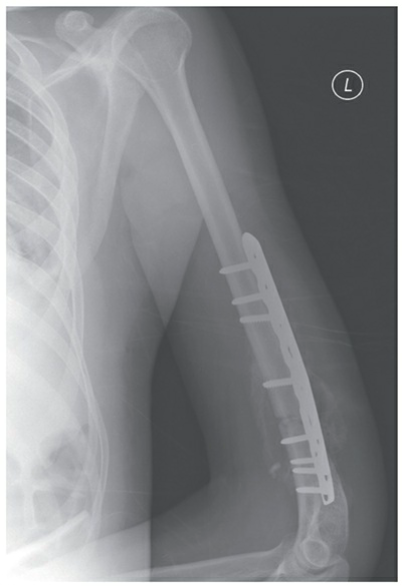

- **Open Reduction and Internal Fixation (ORIF) with Plates and Screws:** A versatile method for anatomical reduction and stable fixation.

🔍 Click to enlargeFigure 4: Plate and screw fixation of a distal third humeral shaft fracture. - **Intramedullary Nailing (IMN):**